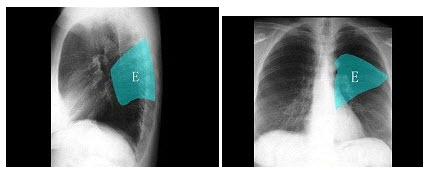

278、单项选择题

如图,在正常胸部X线影像图像上,该英文字母所代表的肺段为()

A.内基底段

B.前基底段

C.外基底段

D.后基底段

E.背段